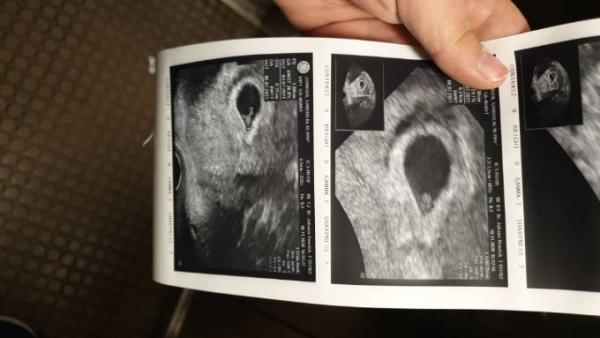

Wir haben heute bei 6+4 einen kräftigen Herzschlag sehen dürfen

Bild zu HERZSCHLAG - Forum für Juli - Mamis